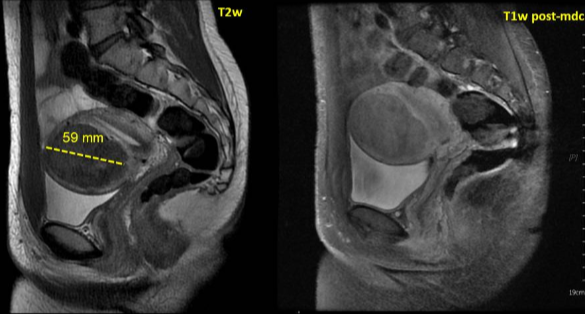

28 岁女性,下腹部疼痛及腹部紧张症状

![]() |

| 治疗前后对比 |

随访

| 6个月和12个月随访 |

44岁,患有盆腔疼痛和阴道出血症状